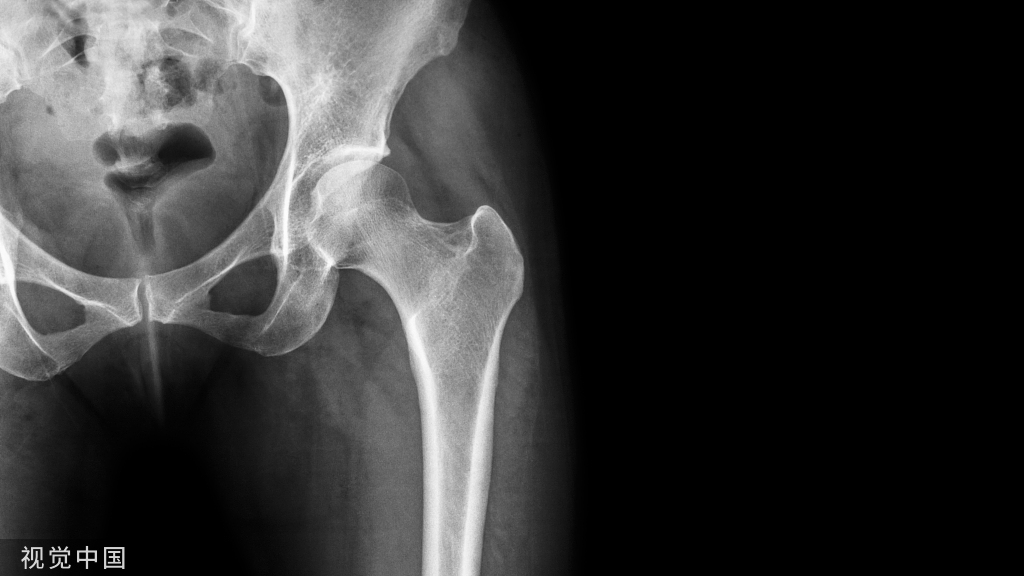

四、股骨内侧髁骨折

股骨内侧髁粉碎性骨折,应用跟骨板复位固定。主要指征是严重粉碎骨折。但如果存在剪切力,单个跟骨板可能不足以 支撑该力。